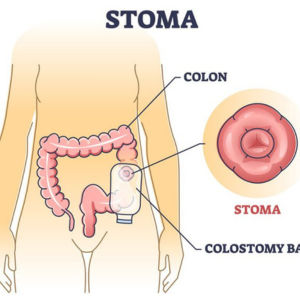

Emergency Colostomy

Stoma Care